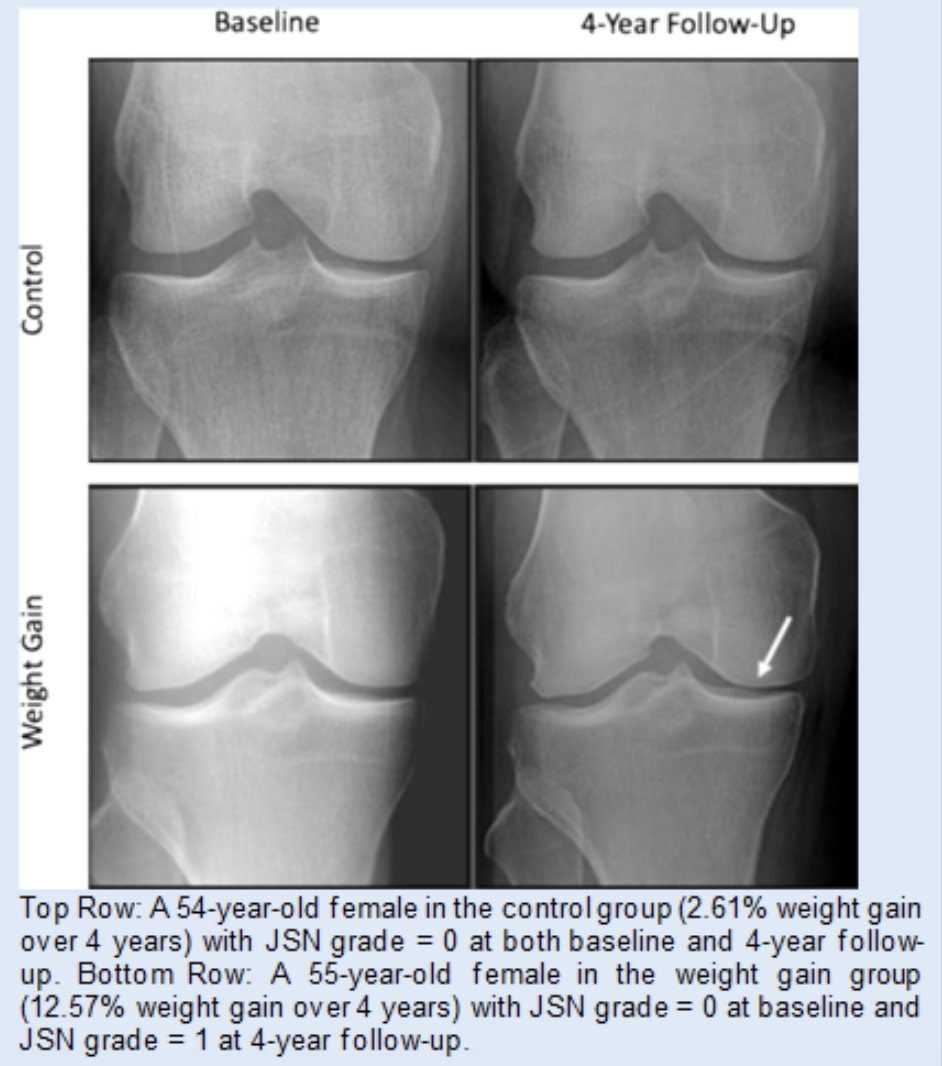

We investigated the effects of weight loss and weight gain on hip and knee radiographic changes, pain, and joint replacement over 4 years in the Osteoarthritis Initiative Cohort. Our results of this large, longitudinal study (n = 2,752 with 4-year follow-up) suggested that weight loss may protect against, and weight gain may exacerbate, radiographic and symptomatic knee OA, while weight change (at a 5% threshold) does not have significant effects on hip OA.